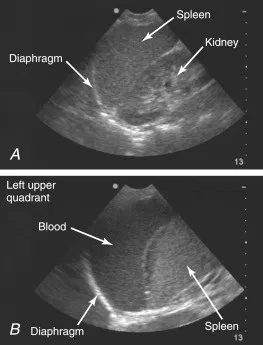

Rate

Rate

Liquide libre abdominal

extended FAST : Focused Assessment with Sonography for efast Trauma

extended FAST : Focused Assessment with Sonography for efast Trauma